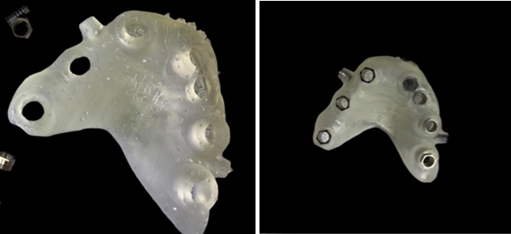

Figure 19: Guide printed with the sleeves and fixations pins placed.

To make sure the printed guide fit precisely, a thorough evaluation was done before the surgery (Figure 20).

Figure 20: Adaptation of the guide in the mouth.

A local anesthetic was given, consisting of 2% lidocaine and 1:100k epinephrine. And fixation pins were drilled and inserted (Figure 21).

Figure 21: Insertion of fixation pins.